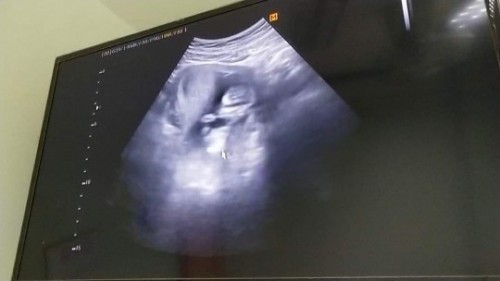

13วีค 5วันค้าา 😍😍

ตอนซาวน์16w6dค่ะ

ภาพตอน10วีคค่ะ

14w3วันค้า❤️

12w6d ฮับบ👶🏻

11w6d จ้าาา

11วีคค่ะ

14วีคค่ะ

13วิคจ้า

10w4d ค่า